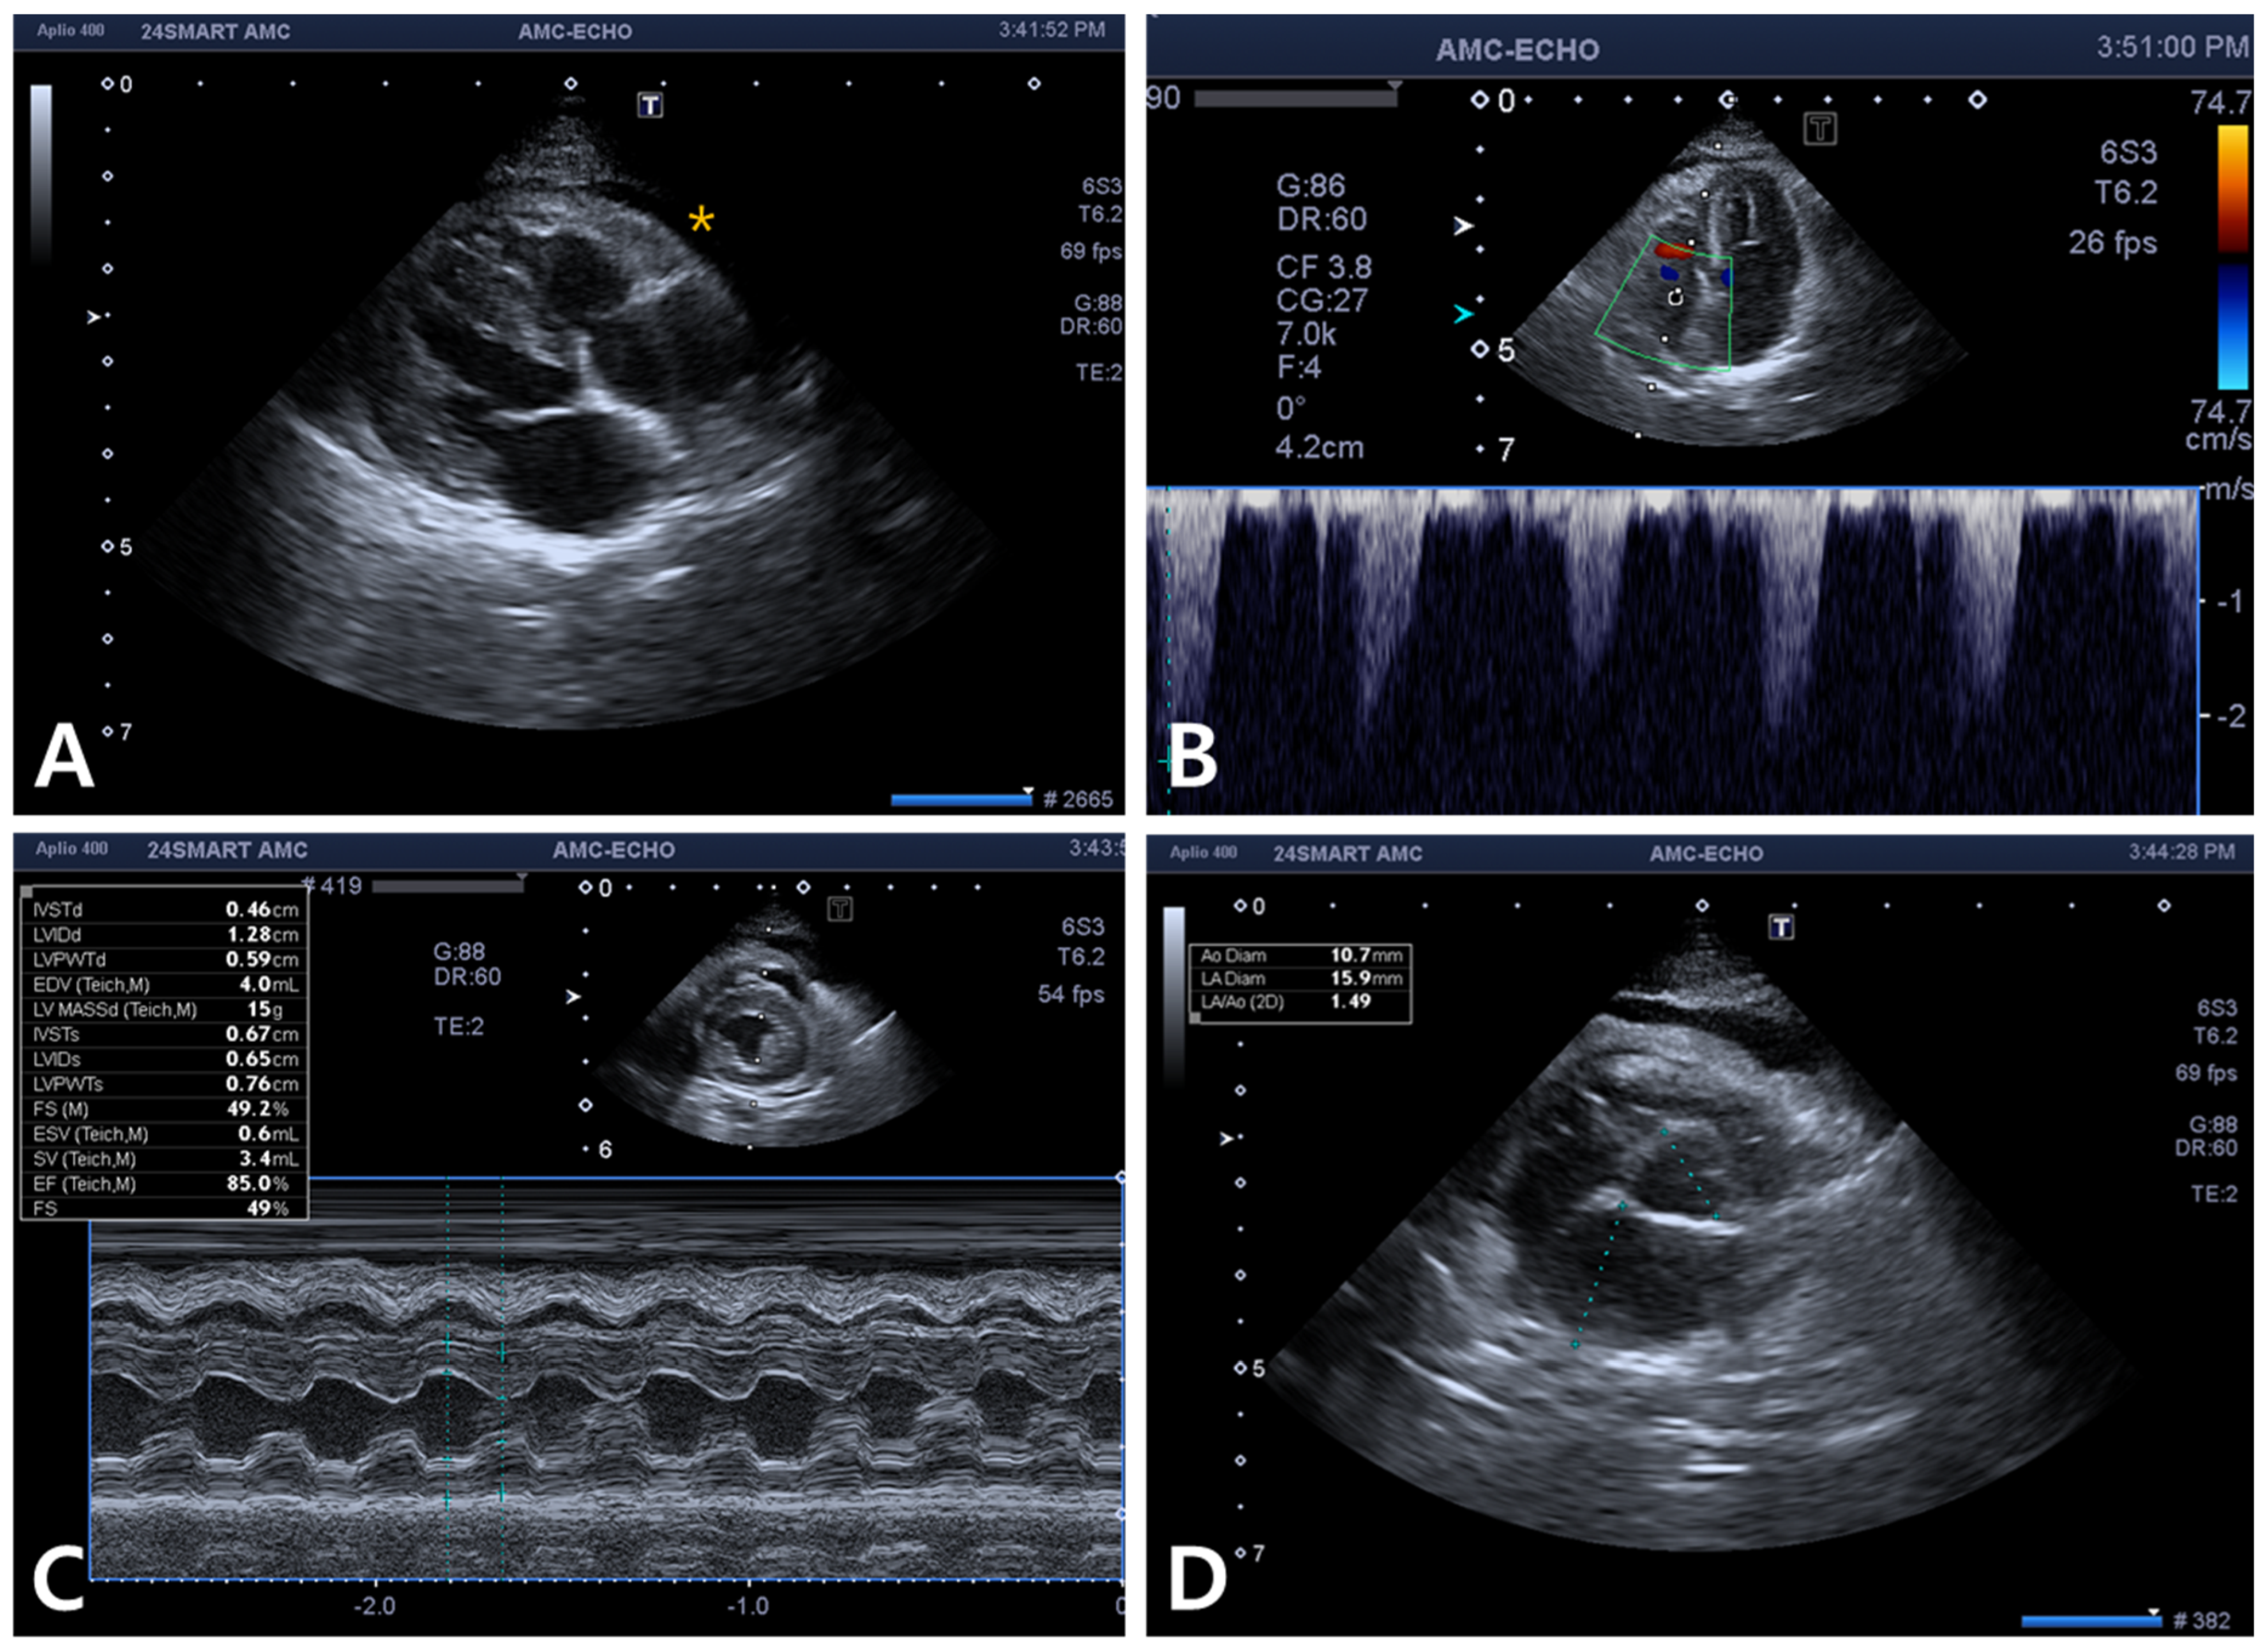

2. Case Description